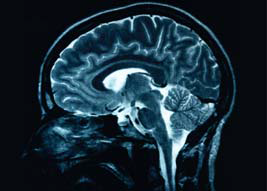

Hemiplegia is a condition best recognized by the story the parents tell and the observations we make when watching children in action. An MRI (magnetic resonance imaging) brain scan is the preferred method of neuroimaging for CP.3 MRI is useful for identifying the presence and location of a brain injury in almost 90% of children with CP.6 Children with hemiplegia commonly have abnormal cranial ultrasounds.